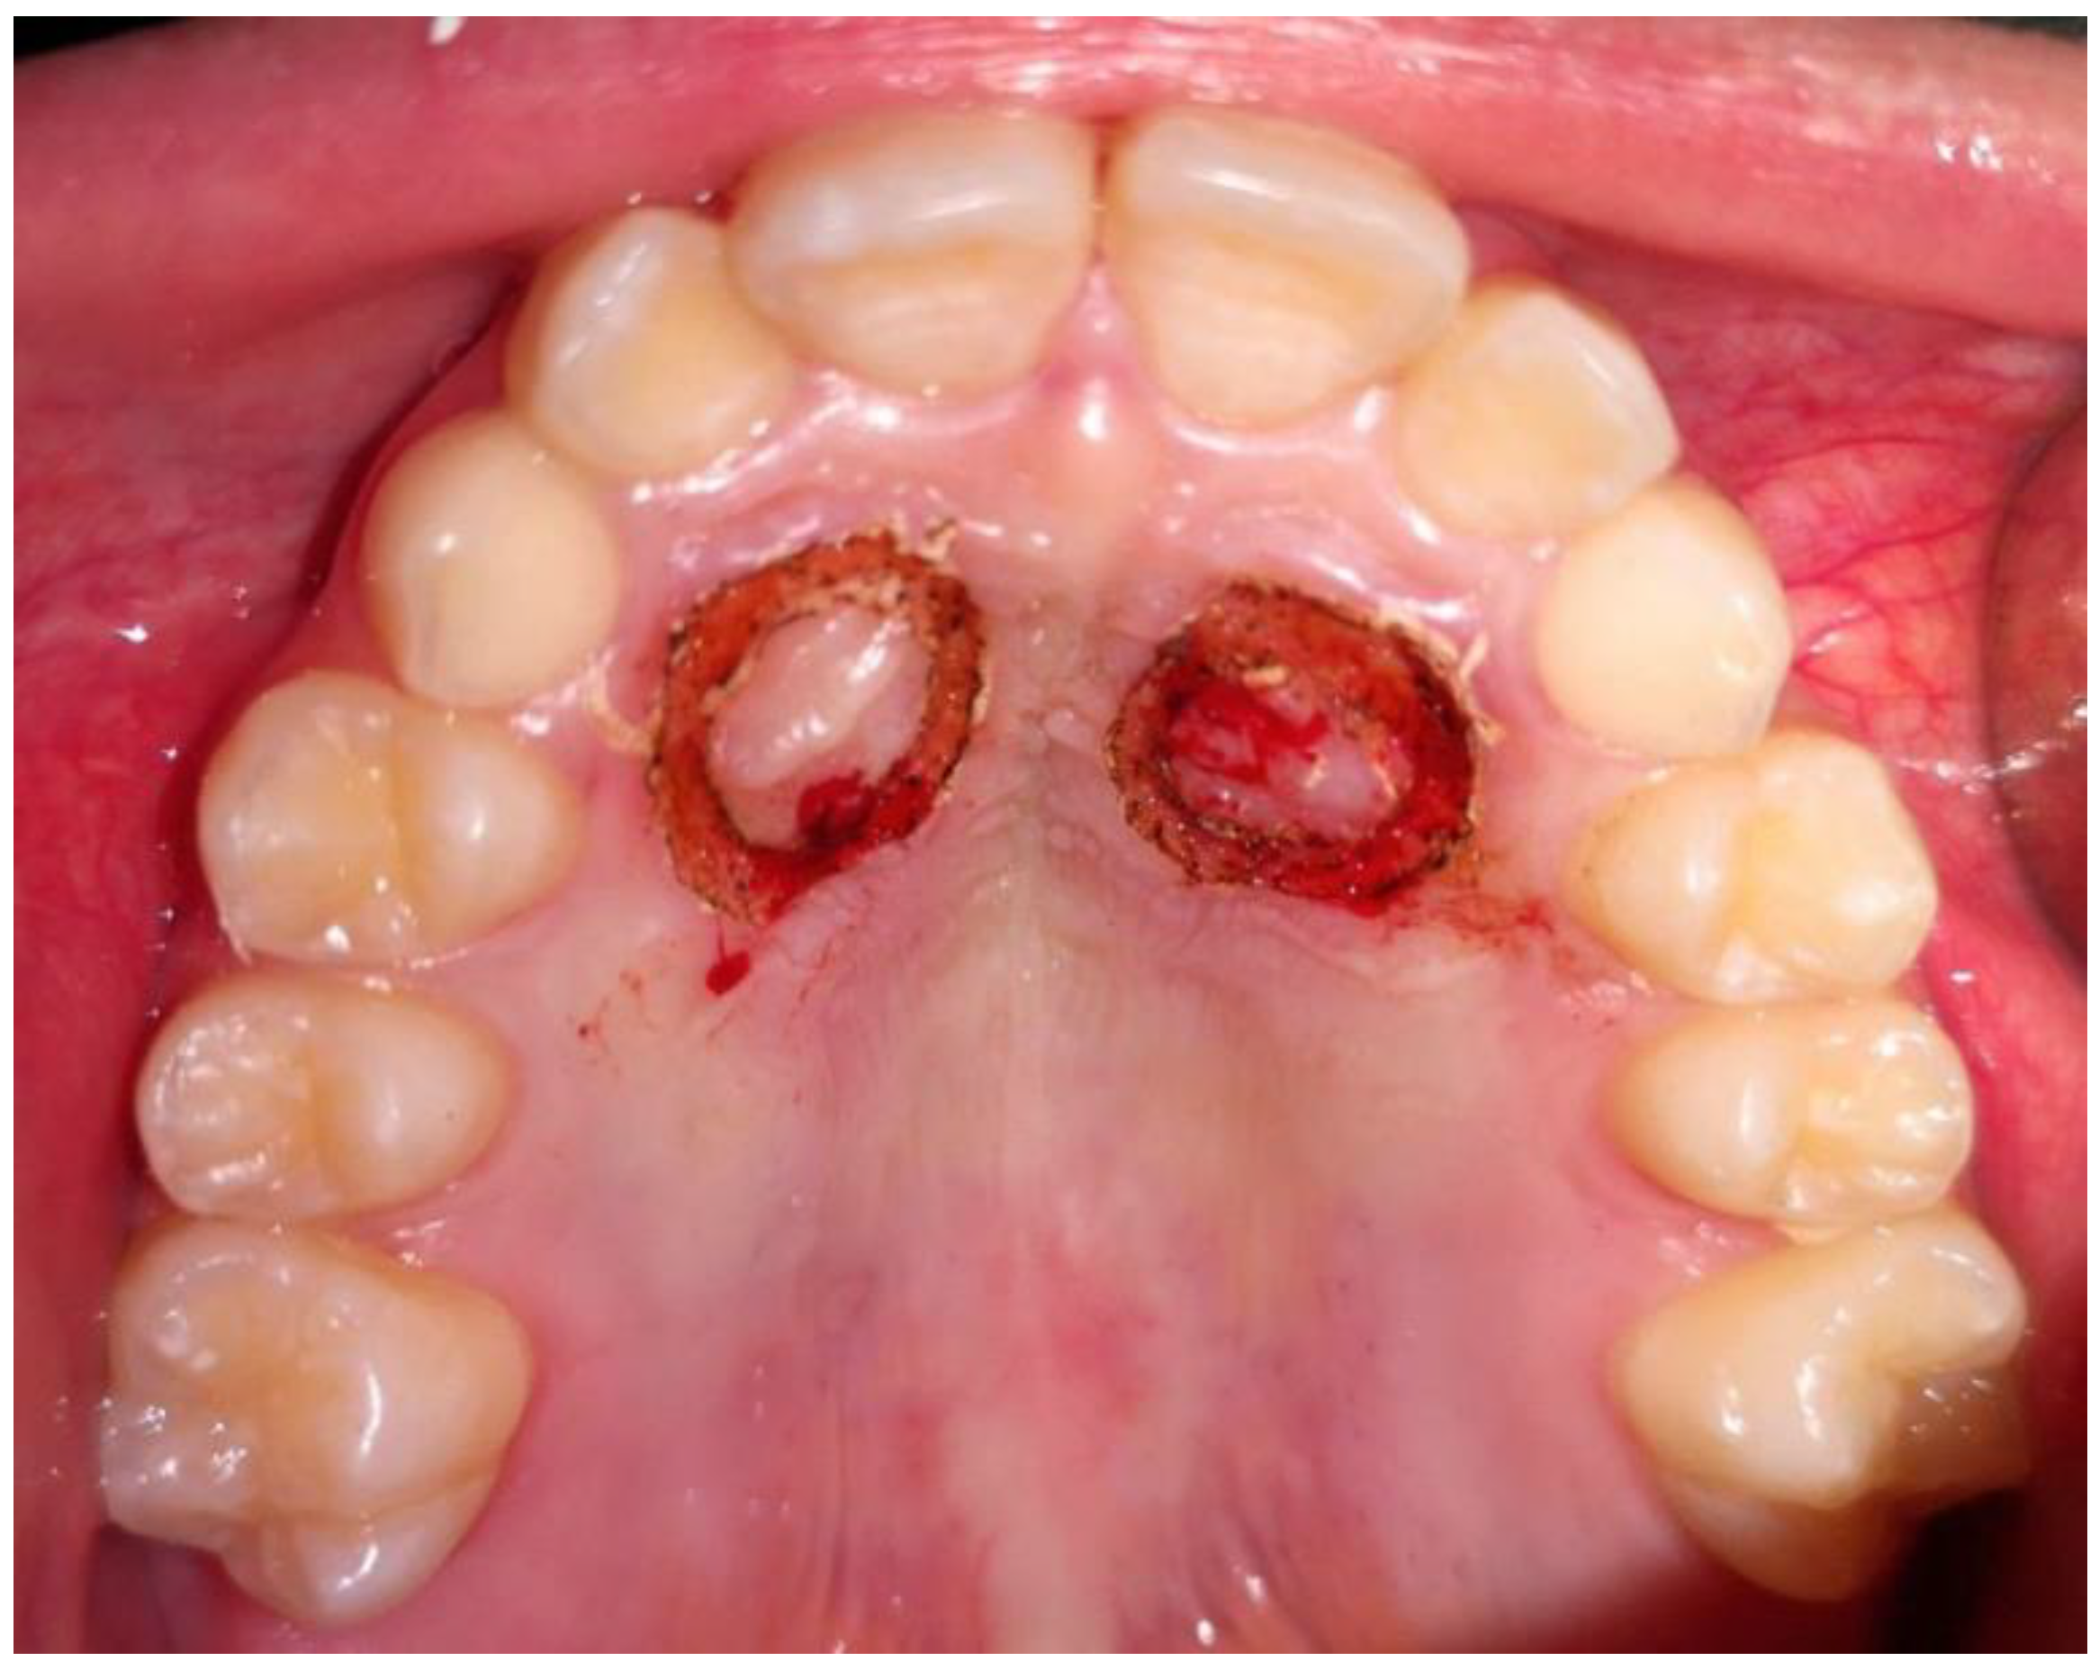

Uncovering and Autonomous Eruption of Palatally Impacted Canines—A Case Report

2. Case Presentation